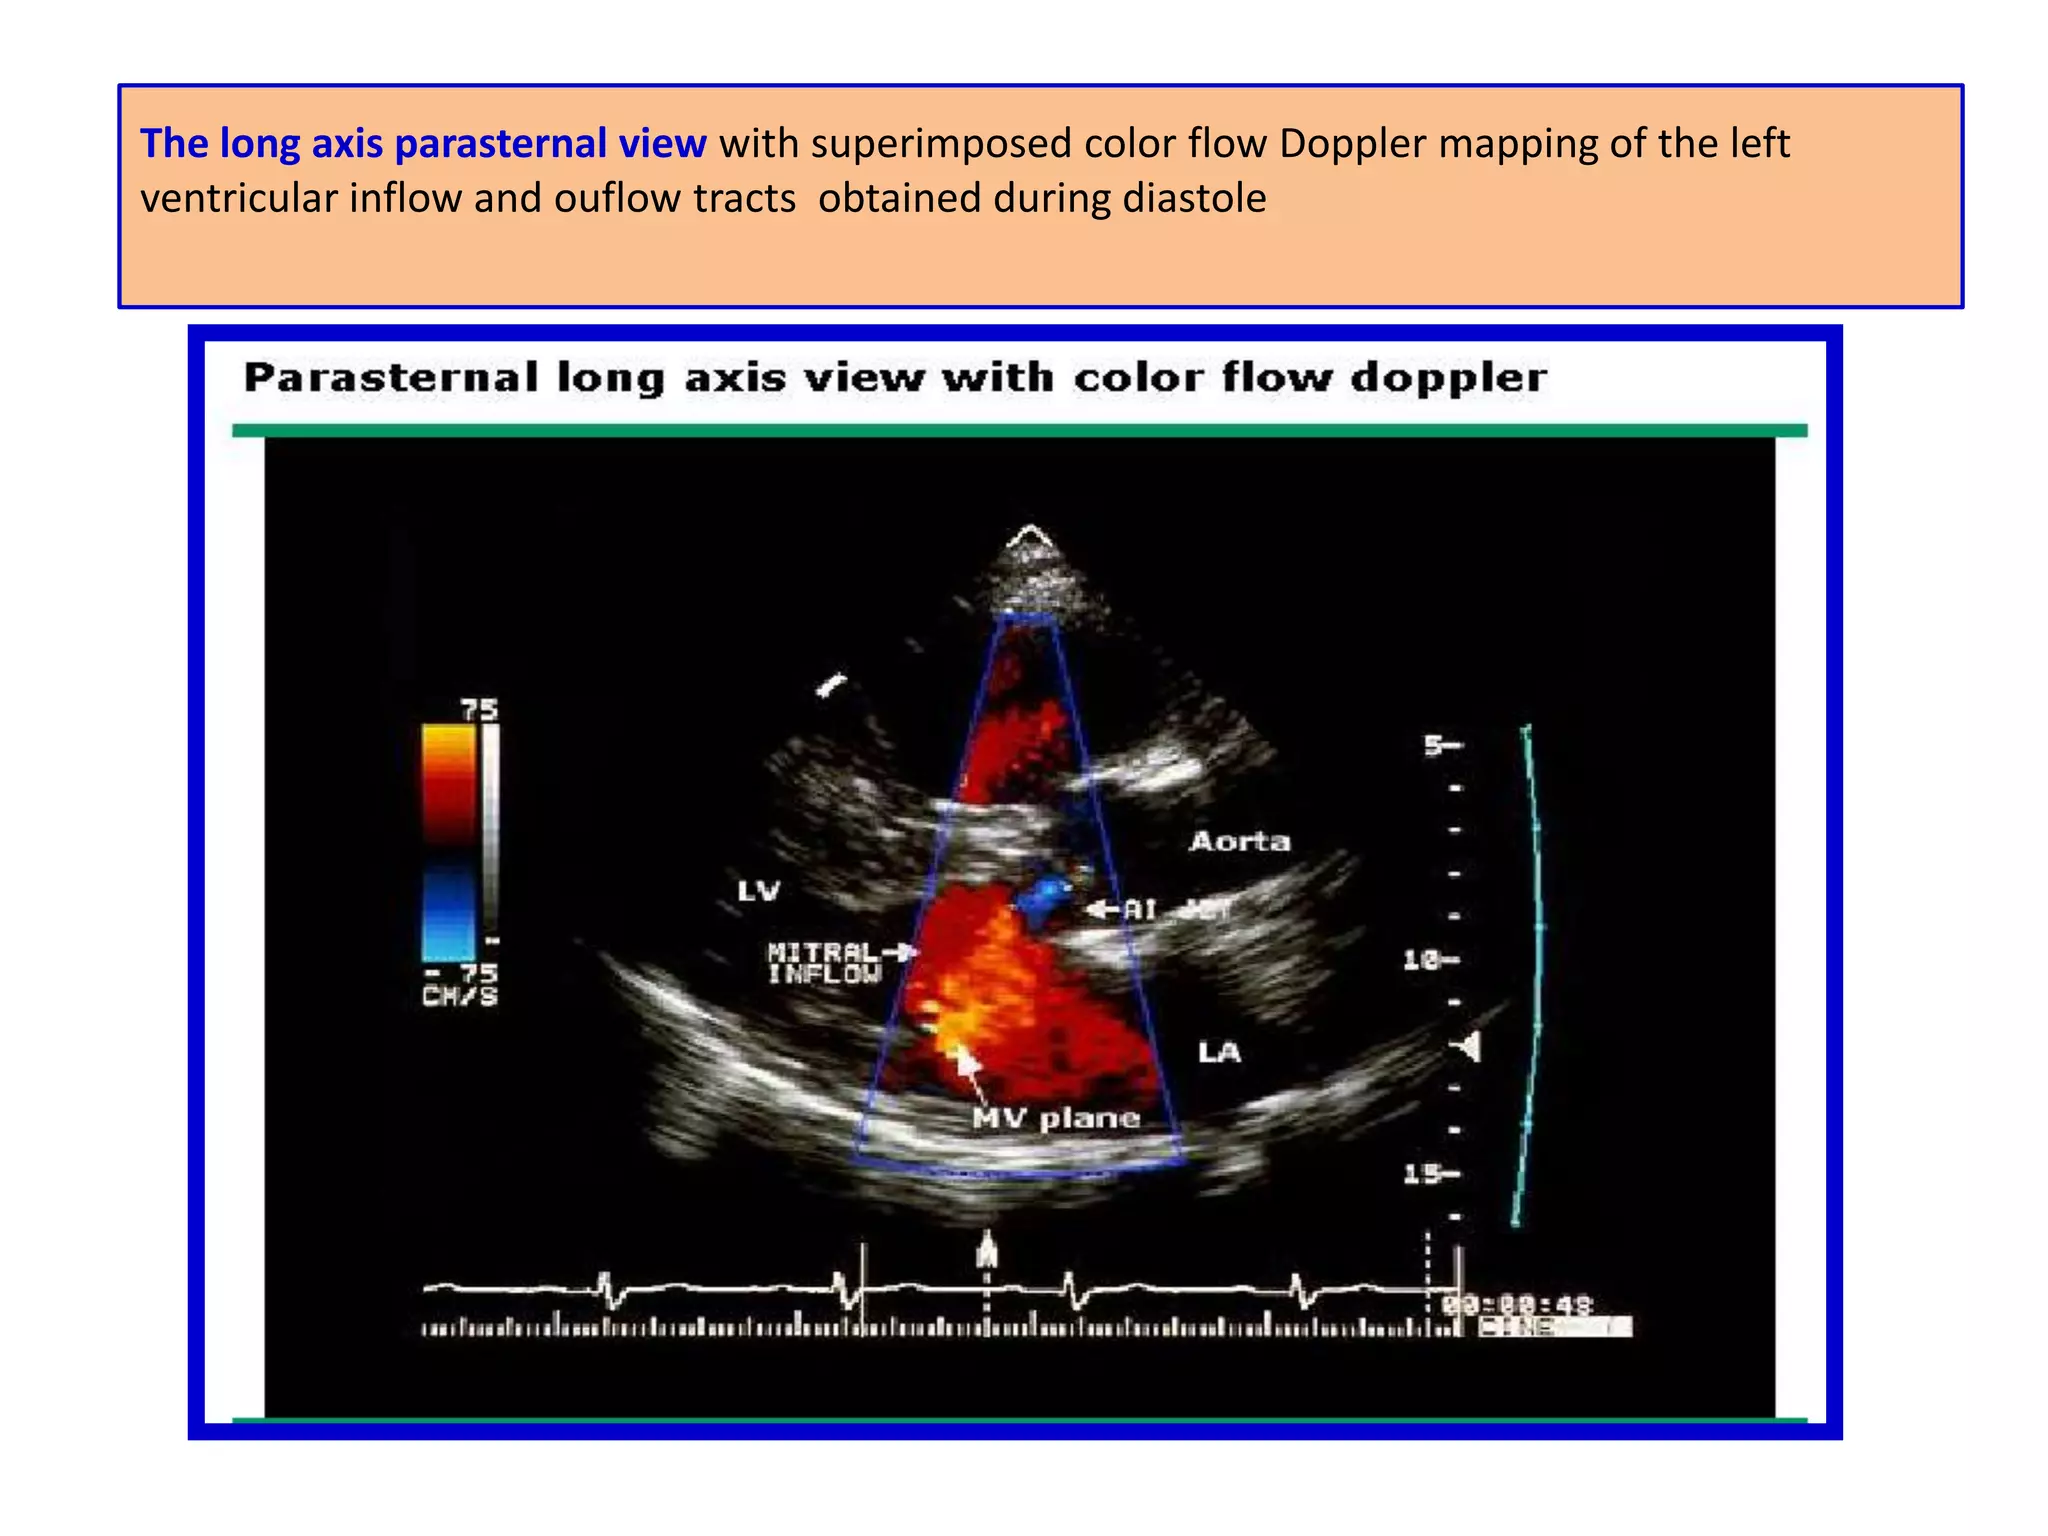

The long axisparasternal view with superimposed color flow Doppler mapping of the left ventricular inflow and ouflow tracts obtained during diastole

the long axisparasternal view of the left ventricular outflow tract during systole; a normal color flow signal (red-orange) is seen in the left ventricular outflow tract. The occasional blue patches in the signal represent aliasing and suggest that the signal is at or exceeds the Nyquist limit.